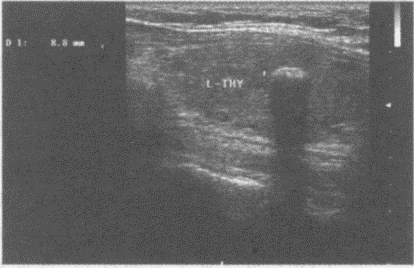

147、单项选择题

结合甲状腺横断面超声声像图,甲状腺为()。

A.均质体

B.非均质体

C.无界面区

D.强回声区

E.以上均不是